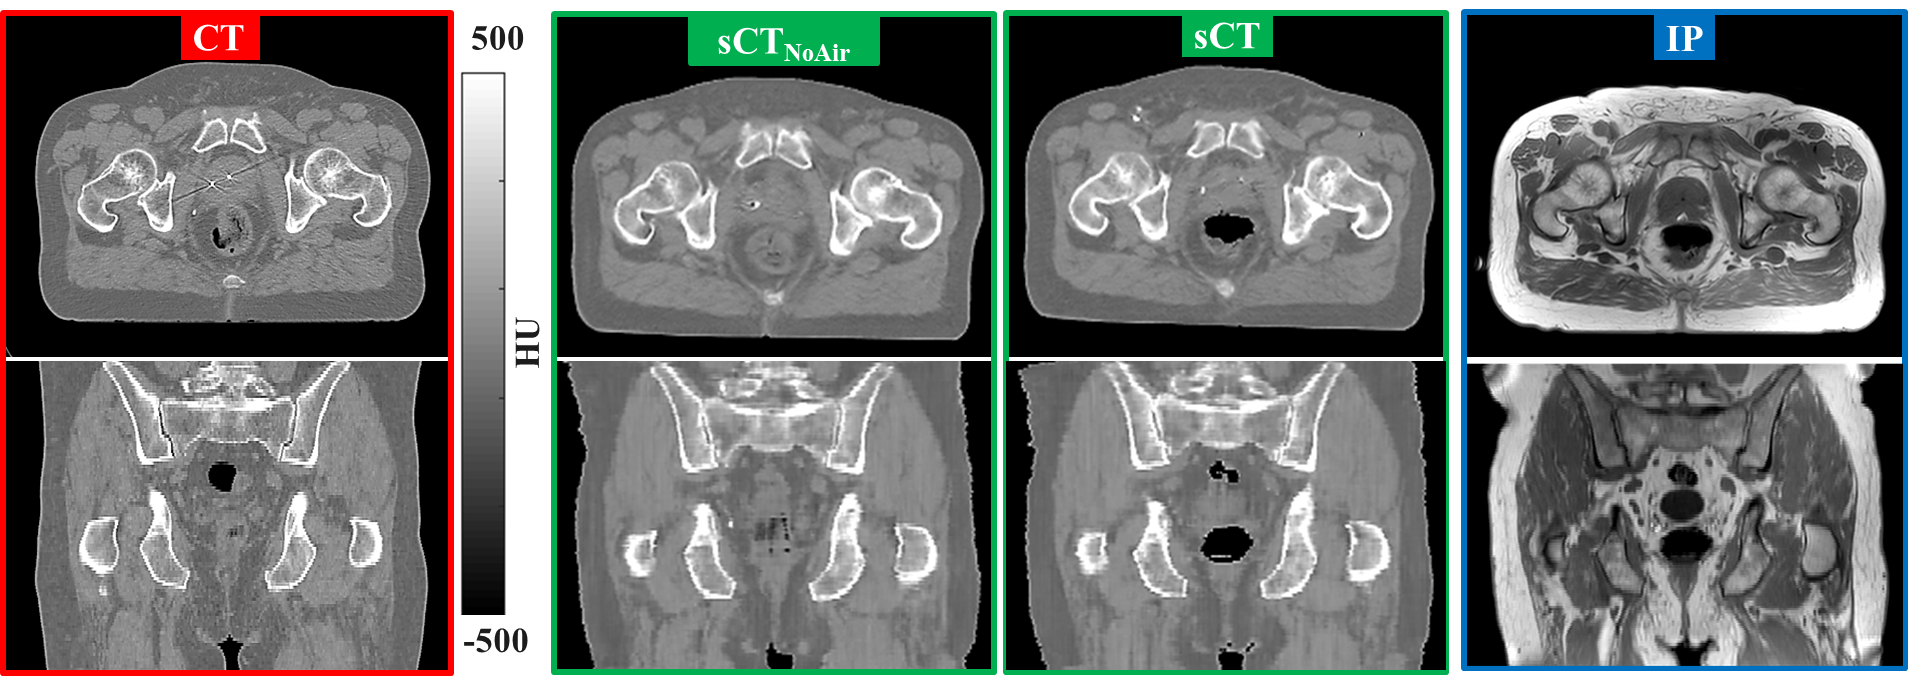

In total, 3495 transverse planes were used for training, which required about 11 hours on the GPU. After cropping the FOV on CT and MR images, each patient was trained using a volume of about 109 transverse planes on average over the training set. After training, inferring the generator network to obtain sCT images was performed in 5.6 s per patient on GPU and four times longer (21 s) on CPU. Fig. 2 presents the transverse (top) and coronal (center) planes of CT (left), sCT (middle) and IP (right) for an exemplary prostate patient. It can be noticed that the different rectal filling between CT and IP is consistent to filling in the sCT image. In the supplementary material, corresponding figures for exemplary rectal and cervical cancer patients are reported.

Tab. 1 reports the statistics of image comparison in terms of MAE and ME in the patient test set between CT/CT and sCT. Over the entire test set (59), the MAE and ME were, on average, 619 and 28 HU. It can be noticed that the MAE and ME are comparable among patients with different tumour location and the MAE decreases when comparing sCT to CT. This demonstrates that CT is more similar to sCT than CT, which justifies its use during the training of the network in a paired fashion.

When considering MEA and ME of the network trained with and withour enforcing air consistency, we observer that the metrics are comparable in the two scenarios, but the ME slightly decreases without enforced air location consistency. This result may be explained by the fact that the size of air pockets is much smaller than the entire body contour. In this sense, voxelwise differences to the air location are not expected to greatly impact the reported MAE and ME. Nevertheless, if we consider Fig. 2, we can observe that air is filled with soft tissue in case training was performed without enforcing air consistency.